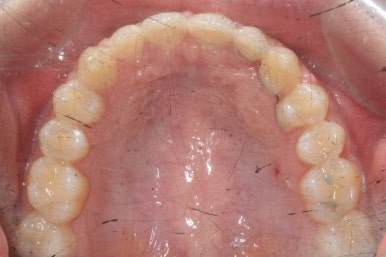

마무리 때의 사진입니다.

윗니만 부분교정하였지만 교합에도 이상 없이 매복되었던 송곳니는 매우 잘 위치를 잡았습니다.

송곳니 부위는 다시 틀어지지 않게 하기 위해 유지철사를 붙여주었습니다.

총 치료기간은 20개월 소요 되었습니다.

부산매복치아교정 상악 부분교정을 통해 매복치를 교정해준 이번 치료의 전후사진 비교입니다.

썩은 유치 대신 영구치 송곳니는 매우 자연스럽게 위치되었습니다. 아랫니는 교정하지 않았기 때문에 약간 삐뚠 느낌은 남아있지만 맞물림은 크게 문제가 없게 마무리 되었습니다.